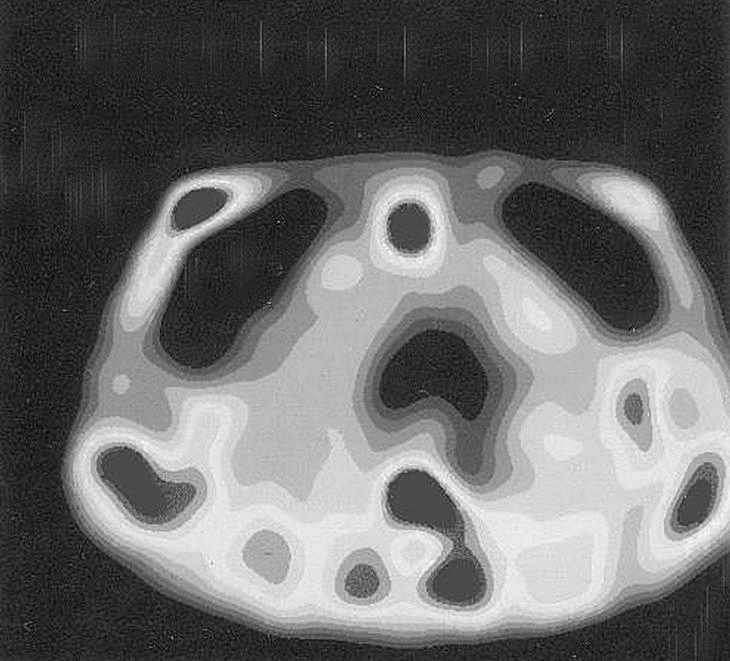

Fig. 2. --SPECT de mama con 99mTc-MIBI. Corte transversal. Foco anormal en la mama derecha (implantes en ambas mamas).